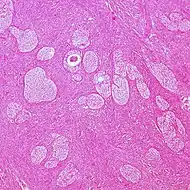

| Adult granulosa cell tumor | 1% | Almost 100% | Small, bland, cuboidal to polygonal cells in various patterns.[9] | ![]() | |